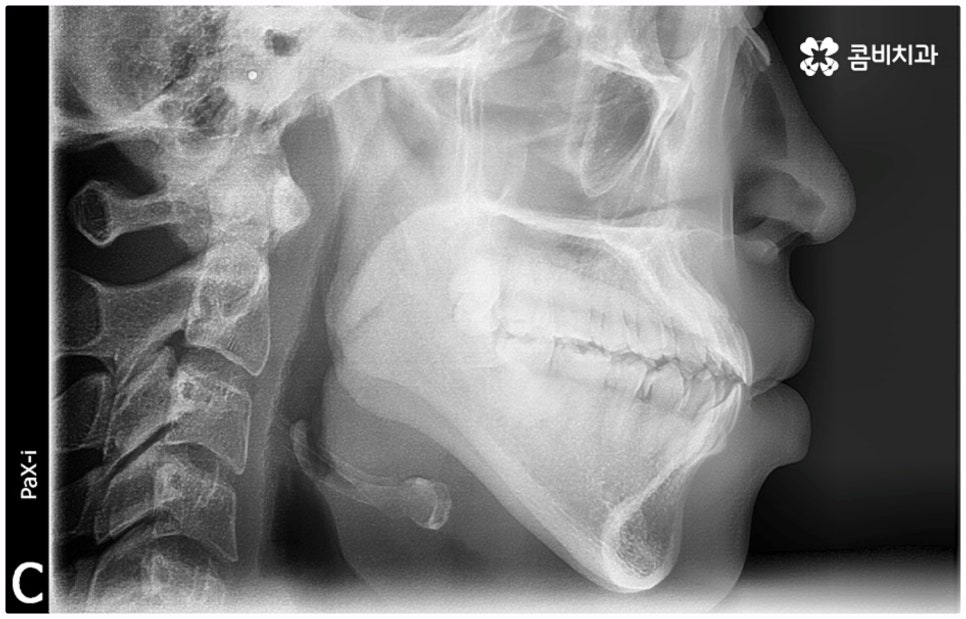

위아래 치아의 교합이 잘 맞지 않는 부정교합을 가지고 있으면 외적인 자신감이 떨어질 뿐 아니라 기능적으로 잘 씹지 못하고 말을 할 때도 발음이 부정확해지는 문제가 생길 수 있기 때문에 교정 치료 등으로 바로잡아 줄 필요가 있어요. 부정교합은 1급, 2급, 3급으로 나눌 수 있는데 오늘은 특히 부정교합 3급 중 절단교합 케이스에 대해 자세하게 알아보려고 하고 있습니다.

부정교합 3급 이란 입을 다물었을 때 아래 어금니가 윗 어금니보다 전방에 위치한 경우를 가리키는 것으로 그 중 절단교합은 이 상태에서 위아래 앞니 끝과 끝이 맞닿는 교합을 의미하는 거예요. 이에 비해 정상적인 교합은 어금니는 똑바로 맞물리고 윗 앞니는 아랫 앞니를 살짝 덮는 정도로 겹쳐지면서 자연스럽게 조금 앞으로 나와 있는 상태를 말하고 있습니다.

이때 심하지 않은 절단교합의 경우 환자분들의 입장에서는 하악이 상악보다 상대적으로 튀어나와 주걱턱처럼 보이는 정도가 그렇게까지 크지는 않다 느끼실 수 있는데요. 특히 또 다른 부정교합 3급 케이스 중 하나인 반대교합 (아래 앞니가 윗 앞니보다 더 앞으로 나가 거꾸로 물리는 경우) 과 비교해 보면 더욱 심각하게 생각되지 않을 수 있어요.

물론 교정 치료에 적기가 정해져 있는 것은 아니기 때문에 성인 이후 중장년 환자분들이라도 교정 치료가 불가능하지는 않으며 상황에 따라 비수술적인 방법으로도 얼마든지 불편함을 줄일 수 있는 경우가 있으니 정확하게 진단한 후 각자에게 맞는 교정 계획을 세워 무리하지 않게 치료를 진행하시길 바라고 있어요. 특히 턱관절과 관련된 부분을 개선하기 위해서는 양악 수술 밖에 방법이 없는 것이 아닌가 생각하셨던 분들이라면 먼저 치과에 내원하셔서 검진과 상담부터 진행해 보시면 마음의 부담을 덜 수 있어 좋을 거예요. 부정교합 3급 치열 (절단교합과 일부 반대교합이 병행되어 있음) 을 가지고 있는 성인분도 교정 치료를 통해 훨씬 자연스럽게 개선이 가능할 수 있으며, 관련 기술 개발 및 미니스크류 등 여러 장치의 발전을 통해 예전에는 적용이 어려웠던 케이스들도 이제는 교정 치료의 도움을 받을 수 있습니다.

치료 계획을 세울 때는 3D CT 같은 정밀 검진 기계를 통해 부정 교합의 정도 및 상하악 관계, 잇몸 건강 상태 등을 꼼꼼하게 살펴보고 회복력과 진행 속도에 영향을 주는 연령, 생활 습관, 평소에 앓고 있는 질환은 없는지 등도 모두 고려하여 세밀한 맞춤 플랜을 세워야 하며 같은 주걱턱 증상이라도 심각한 정도와 턱의 모양에 따라 교정 방법이 달라질 수 있는 만큼 다양한 케이스를 다뤄본 임상 경험을 바탕으로 높은 기술력을 가지고 있는 의료진에게 교정 치료를 받는 것이 굉장히 중요한 포인트라고 할 수 있어요. 정밀 검진 장비 보유 여부, 술자의 뛰어난 숙련도와 함께 체계적인 교정 시스템을 갖추고 사후 관리를 철저하게 해 주는 치과에서 처음부터 끝까지 무리하지 않게 치료를 받는 것도 중요하니 이런 부분도 체크해 보시길 권유드리고 있습니다.